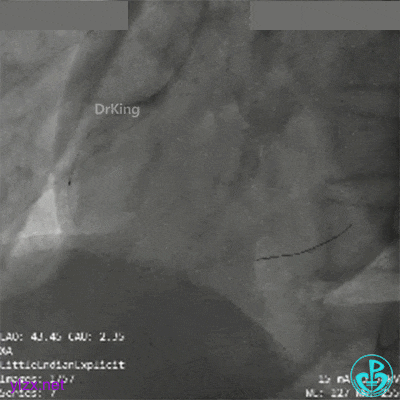

冠脉造影

RCA第一转折50%狭窄,第二转折前100%闭塞。